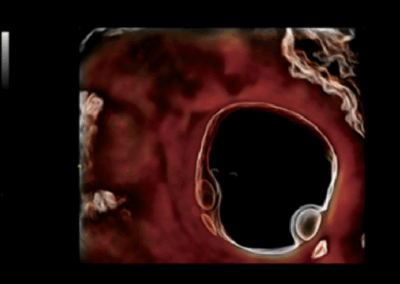

Nuewa i8

El Nuewa I8, ofrece una claridad de imagen inigualable, elevando tu confianza y eficiencia a nuevas alturas. Diseñado con el máximo cuidado, minimiza la fatiga y maximiza la conveniencia a lo largo del proceso de operación.

Impulsado por la innovadora plataforma ZST + y un conjunto completo de soluciones inteligentes, el Nuewa I8 ofrece una claridad de imagen inigualable, impulsando tu confianza y eficiencia a nuevas cotas. Diseñado con la máxima atención al detalle, minimiza la fatiga y maximiza la comodidad durante todo el proceso quirúrgico.